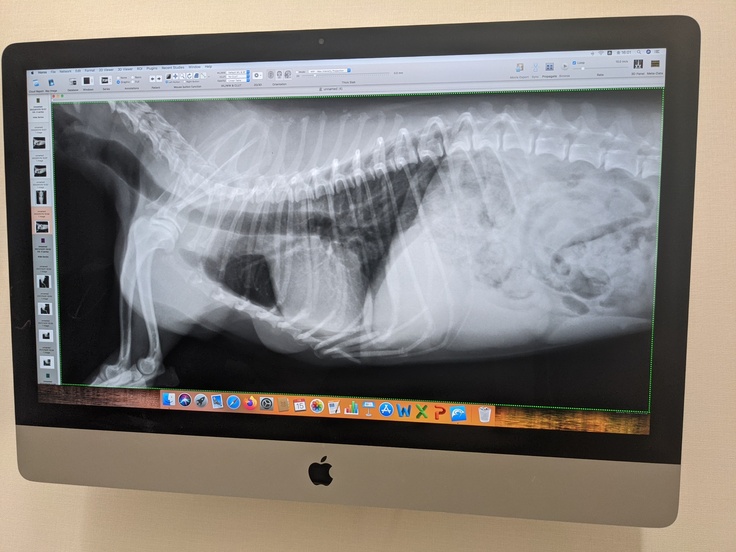

⚫レントゲン撮影は、7月15日に診察受けた時のものです。幸いに、肺に転移はみられないようでした。ご報告致します。

乳腺腫瘍の場合は、CTは撮らないそうです。

乳腺切除手術の術前検査は

・採血すみ

・レントゲン撮影すみ

・心電図すみ